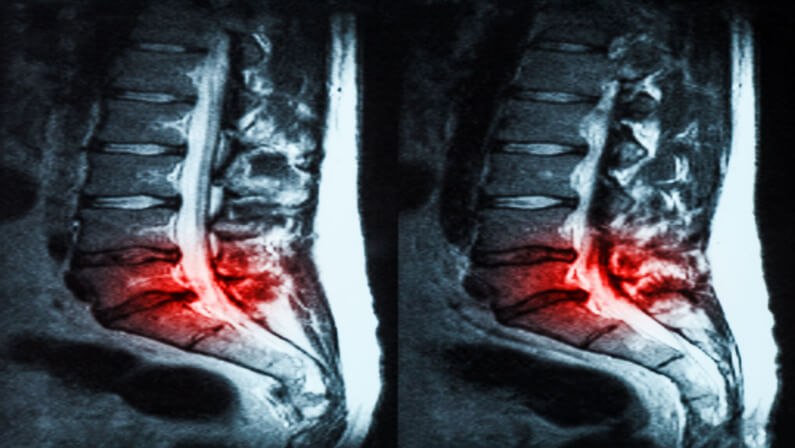

Herniated discs are frequently diagnosed and monitored with MRI scans. Finding the location of the herniated disc(s) in the spine and the level of nerve compression is one of the most frequent uses for them.

A herniated disc can also be seen on an MRI scan or other advanced imaging test. Your doctor may ask for an MRI to get a better idea of where the herniated disc is and how bad it is.

For a patient to be able to correctly read a lumbar MRI scan for a herniated disc, they must have a basic understanding of how the lumbar spine is built.

In the lower back, there are 5 vertebrae that are connected by facet and disc joints. Most of the time, these discs are in constant motion, which causes wear and tear. When the outer layer of the disc is torn, this is called an annular tear.

When this happens, the jelly-like center of the disc squeezes out into the spinal canal, causing a hernia. An MRI scan will often show this hernia as a spot that stands out.